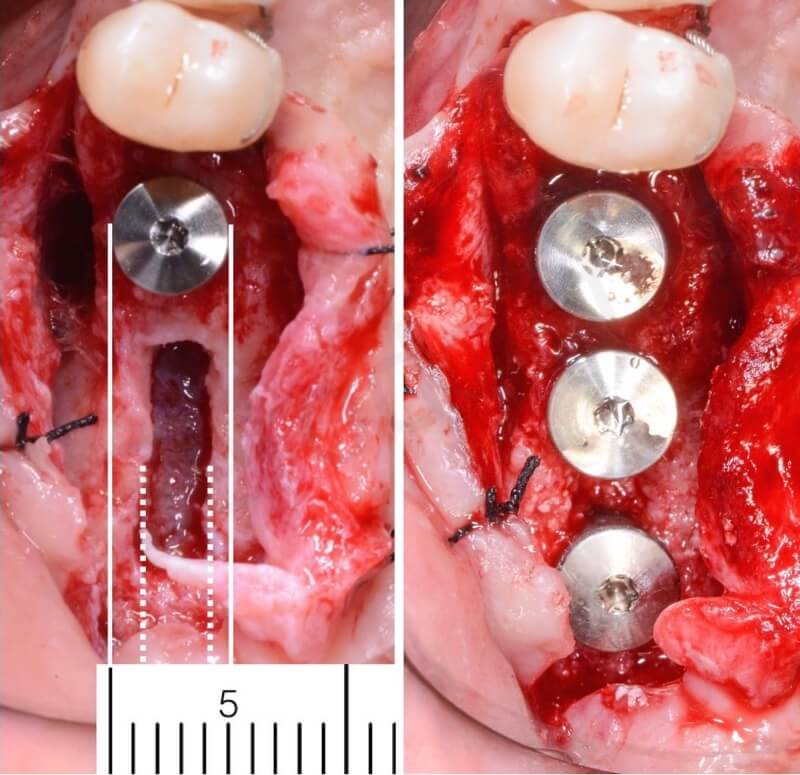

In this case 3 Straumann Tissue Level Tapered Effect Implants have been placed.

A very important thing: you need to use tapered implants. The window’s size should allows the insertion of the end of the implant but must be lower than the diameter of the implants’ neck.

Sinus lift crestal approach

sinus lift crestal window

Implant placement